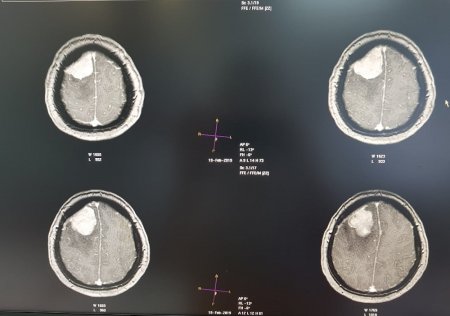

Опухоль мозга диаметром семь сантиметров удалили пенсионерке врачи Мангистау

Дополнительное обследование в аппарате компьютерной томографии (КТ) и магнитно-резонансной томографии (МРТ) показали у пенсионерки наличие отека правого полушария головного мозга.

- Врачи 28 февраля провели операцию по удалению опухоли в правой лобно-теменной области путем костно-пластической трепанации черепа пациентки. Операция прошла успешно, без осложнений, опухоль удалена полностью, - отметили в пресс-службе управления здравоохранения.